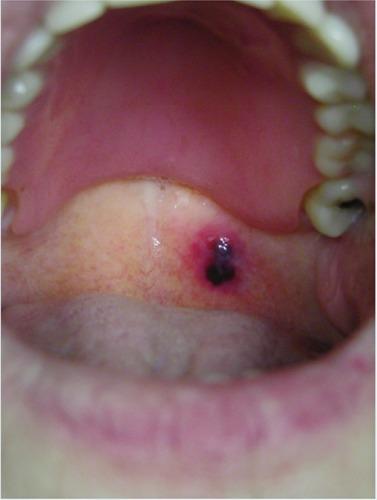

Angina bullosa hemorrhagica is a rare and benign disorder, usually localized in the subepithelial layer of the oral, pharyngeal and esophageal mucosa. The lesions are characterized by their sudden onset. They appear as a painless, tense, dark red and blood-filled blister in the mouth that rapidly expand and rupture spontaneously in 24-48 hours. The underlying etiopathology remains ill defined, although it may be a multifactorial phenomenon including diabetes, and steroid inhalers. The condition is not attributable to blood dyscrasias, nor other vesicular-bullous disorders. In this study, eleven patients with such blisters are described. Physical examination of the patients revealed a single blister with hemorrhagic content localized in the oral mucosa. Biopsy of the lesions showed sub epithelial blisters with a mild infiltrate. In general practice, dermatologists could face a blood-filled bullous lesion of the oral mucosa. Recognition is, therefore, of great importance for dermatologists.

出血性大疱性心绞痛是一种罕见的良性疾病,通常局限于口腔、咽部和食管黏膜的上皮下层。病变的特点是突然发作。它们表现为口腔内无痛、紧张、暗红色且充满血液的水疱,在24 - 48小时内迅速扩大并自发破裂。尽管其潜在病因可能是包括糖尿病和类固醇吸入器在内的多因素现象,但其确切病因仍不明确。该病症与血液系统疾病或其他水疱大疱性疾病无关。在本研究中,描述了11例有此类水疱的患者。对患者的体格检查发现口腔黏膜有一个充满血性内容物的单个水疱。病变活检显示上皮下疱伴轻度浸润。在一般临床实践中,皮肤科医生可能会遇到口腔黏膜充满血液的大疱性病变。因此,识别对于皮肤科医生非常重要。